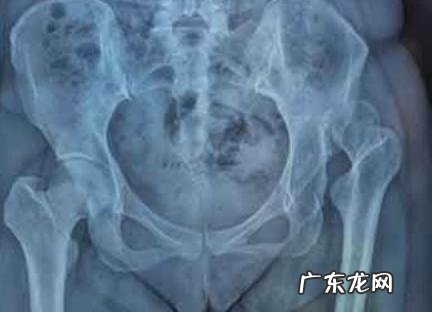

尾骨骨折能蹲着大便吗:

尾骨骨折能蹲着大便 。 实际上 , 对于这种类型的患者 , 医生通常建议蹲便排便 , 因为此时与坐姿和站立相关的所有姿势都可能刺激骨折端 , 引起严重的疼痛 , 并可能导致骨折无法愈合 。

尾骨骨折的患者蹲下时不会严重刺激骨折部位 。 当然 , 在深蹲过程中不可避免地会产生一定程度的疼痛 , 但是这种疼痛与坐着有关 。 也就是说 , 这种疼痛要轻得多 , 因此对于这类患者来说 , 深蹲更好 。